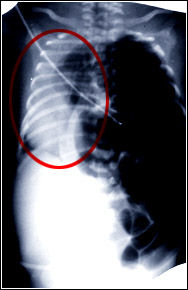

Defecto de desarrollo del diafragma que deja comunicada las cavidades toráxica y abdominal. La radiografia muestra la situación de vísceras abdominales en el tórax, que comprimen al corazón y al pulmón en el hemitórax derecho (círculo rojo).